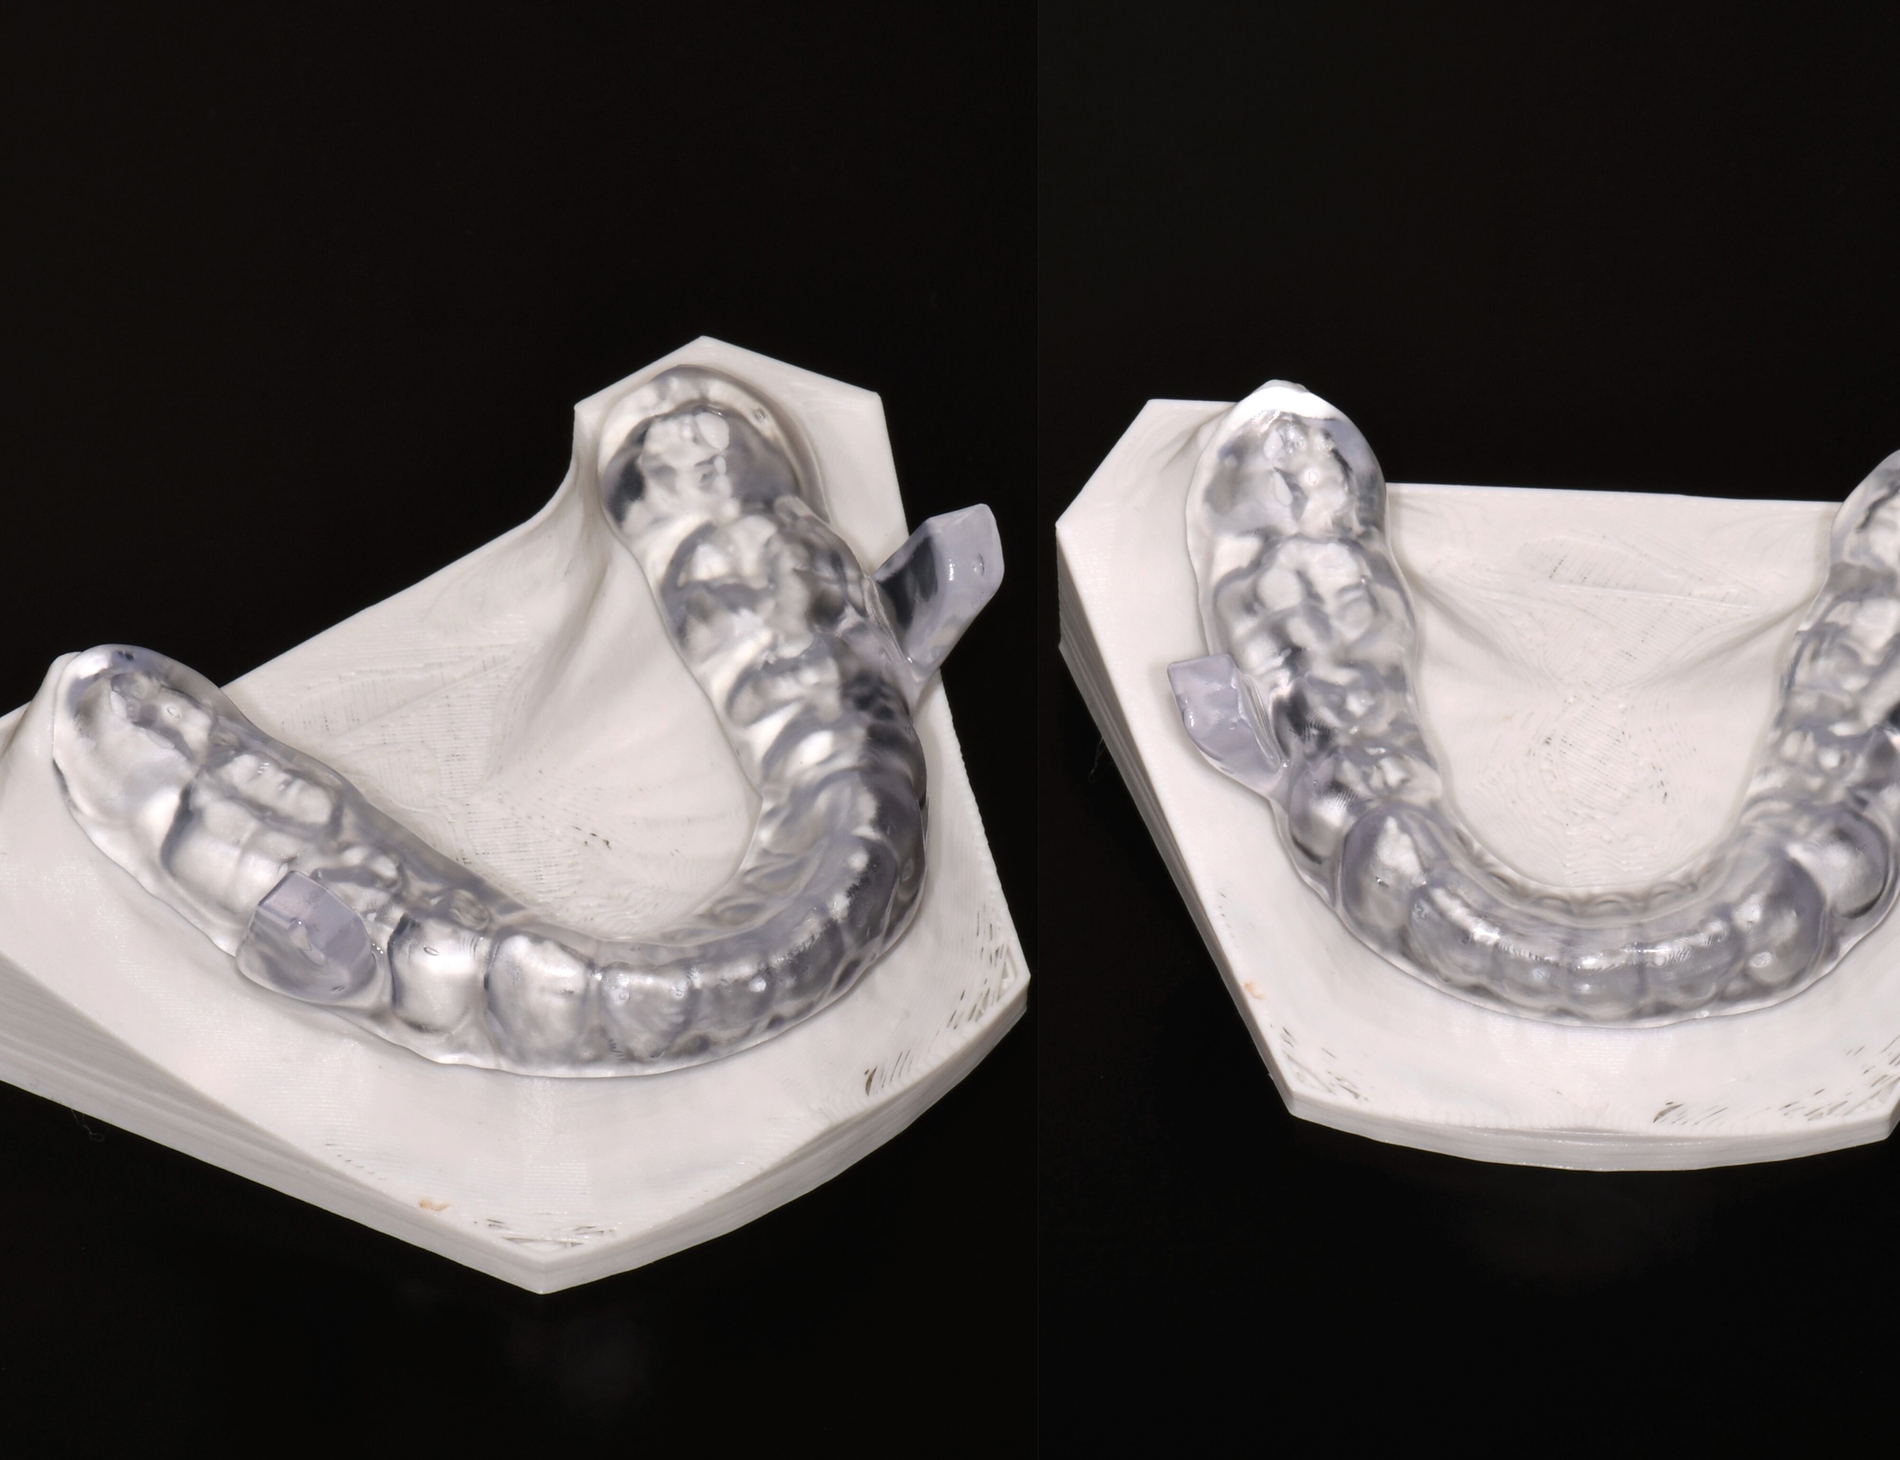

Festsitzende Retainer

Auch für die Herstellung von Retainern sind bereits vielfältige 3-D-gedruckte Lösungen vorgestellt worden. Der Nachteil liegt hier jedoch hauptsächlich in der Verwendung von steifen Materialien. Im Gegensatz zu flexiblen konventionellen handgebogenen Retainern werden die auftretenden Kaufkräfte in höherer Weise direkt auf den Adhäsivverbund weitergeleitet, was die Gefahr eines Klebeversagens erhöht [Hetzler et al., 2024].

Dies ist besonders für Retainer von hoher Relevanz, da sie im Regelfall lebenslang in situ verbleiben und auftretende Komplikationen oft zu spät entdeckt werden, wodurch sich die Gefahr eines Rezidivs erhöht. Bisher eigens durchgeführte Studien deuten auf deutliche Nachteile in der Langzeit- und Maximalstabilität 3-D-gedruckter Retainer hin [Roser et al., 2023]. Zudem ist die Zahnmobilität unter den meisten CAD/CAM-Retainern deutlich stärker eingeschränkt [Roser et al.. 2023]. Der Anspruch flexiblerer 3-D-druckbarer Materialien für einen suffizienten klinischen Einsatz muss somit erst noch erfüllt werden.